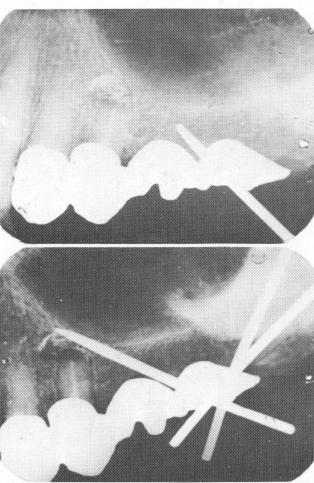

Fig. 15-62. A, The first pin was radiographed a number of times in order to be certain that it would be driven between the tooth apex and the floor of the sinus. B, The periapical radiograph showing the three pins in their proper positions. The ends protruding through the template were cut short so that they would not interfere with the fitting of the superstructure. (From Linkow, L. I.: Atypical implantations for anatomically contraindicated situations, Dent. Concepts, Fall, 1967.)

A

B

1 Endosseous upper pin implant driven through template anteroposteriorly

2 Periapical radiograph shows endosseous pin implants in position